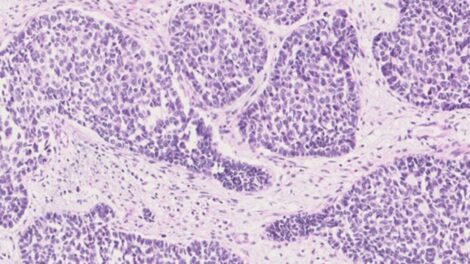

Professor Yaohe Wang, Dr Jun (Alex) Wang and team published new results revealing that oesophageal squamous cell carcinoma (ESCC), is composed of four distinct subtypes, paving the way to more personalised treatments.